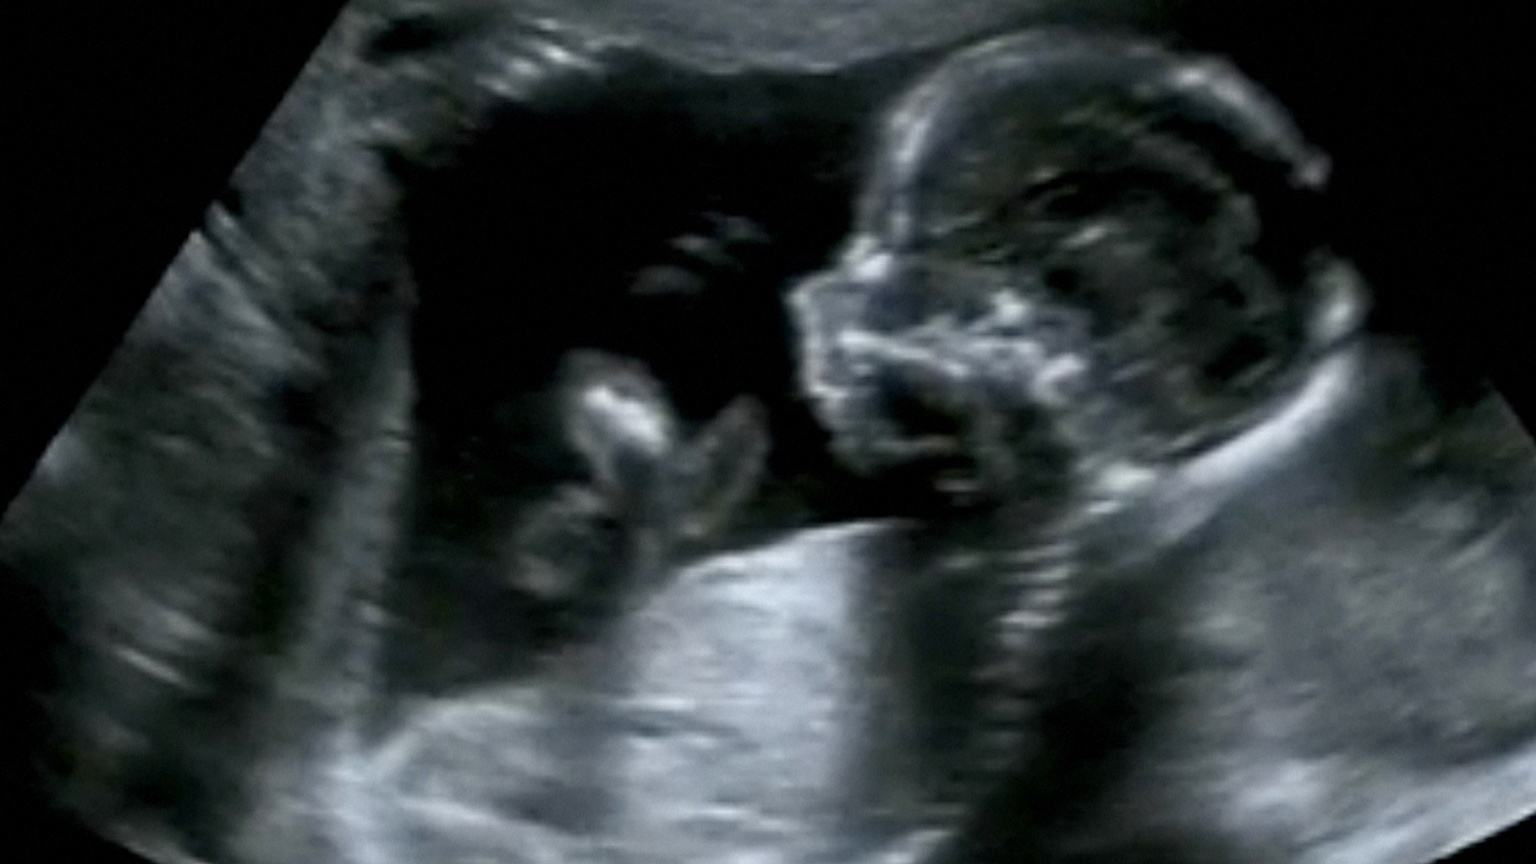

How Pollution Affects the Unborn

"Before children even take their first breath, common air pollutants breathed by their mothers during pregnancy may reduce their intelligence." Scientific America reports on urban pollution.